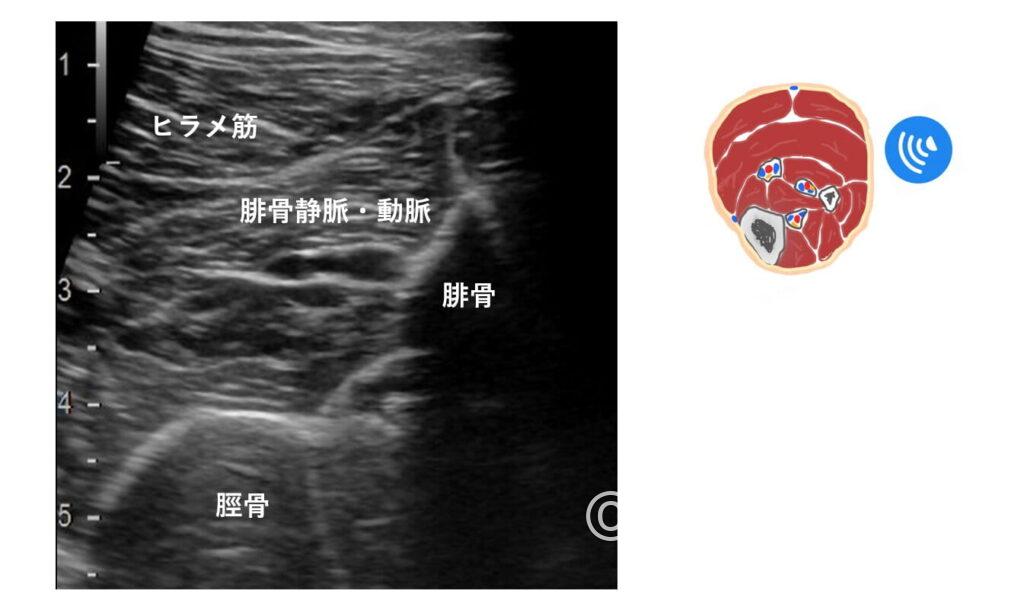

特に【後脛骨静脈】と【腓骨静脈】でしょうか。

脛骨は円弧状、腓骨は鋭角に見える(大昔に他施設さんへ研修へ伺った際、教えていただいた先生は腓骨を『富士山』と表現していました)

なので、側を走行している血管はそれぞれ後脛骨静脈(前脛骨はふくらはぎからではなく下腿前面からスキャンすれば描出できます)、腓骨静脈と考えられます。

ただ、後脛骨静脈は脛骨から少し離れているので少し難しい印象。